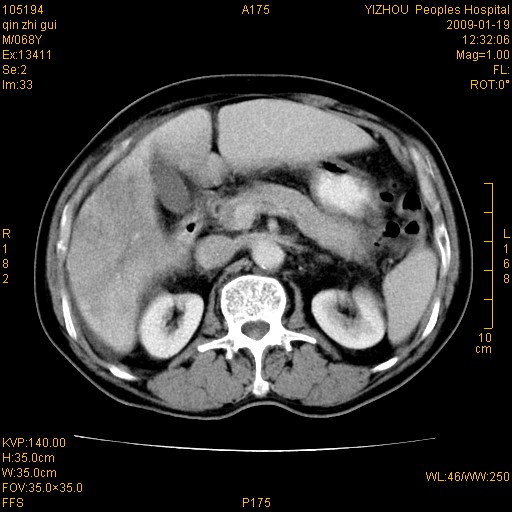

以下是引用随光逐影在2009-1-21 16:11:00的发言:[br]1)考虑肝右叶肝癌并肝静脉及门静脉瘤栓形成。2)肝硬化,少量腹水。3)胆囊炎。4)右侧少量胸腔积液。

病灶外缘凹凸不平,平扫低密度,增强动脉期有强化,门脉早显,静脉期及延期呈延迟强化,结合病史考虑右肝前叶巨块型肝癌可能性大,强化表现不除外胆管细胞癌